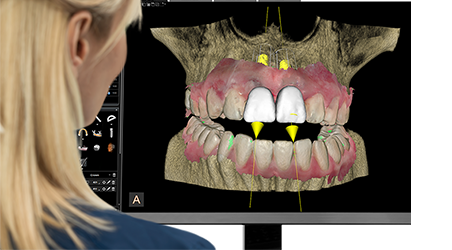

4. อินเทอร์เฟซใช้งานง่าย หน้าจอเดียวควบคุมทุกฟังก์ชัน ทำให้ใช้งานได้อย่างสะดวก รวดเร็ว แม้สำหรับผู้เริ่มต้น

• ระบบเปิด (Open Platform) สามารถเชื่อมต่อกับซอฟต์แวร์ CS Imaging เวอร์ชัน 8 และเครื่องสแกนช่องปากจากหลายแบรนด์ได้

• ซอฟต์แวร์เสริม รองรับโมดูลเพิ่ม เช่น: Prosthetic-Driven Implant Planning (PDIP), CS Airway Module (สำหรับวิเคราะห์ทางเดินหายใจ)